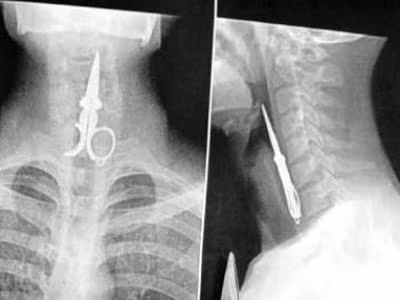

Tai nạn tai hại chảy ra với người đàn ông Trung Quốc khi mượn một chiếc kéo cắt móng tay dài khoảng 10,2 cm thay vì dùng tăm xỉa răng sau bữa ăn. Sặc cười mà anh đã nuốt chửng luôn chiếc kéo đó. Rất may bác sỹ gắp nó ra kịp thời.